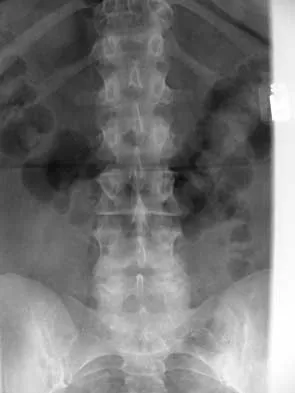

Master AAOS & ABOS boards with high-yield practice MCQs for Set 4, focusing on cervical & thoracolumbar verte…

Master AAOS, ABOS & OITE boards with Set 3 spine surgery MCQs. Covers degenerative spinal conditions, vertebr…

Master AAOS & ABOS boards with high-yield MCQs for Set 2. Review crucial topics like lumbar stenosis, cervica…

Master AAOS & ABOS Spine Surgery boards with Set 1 practice MCQs. Covers degenerative spine conditions, traum…